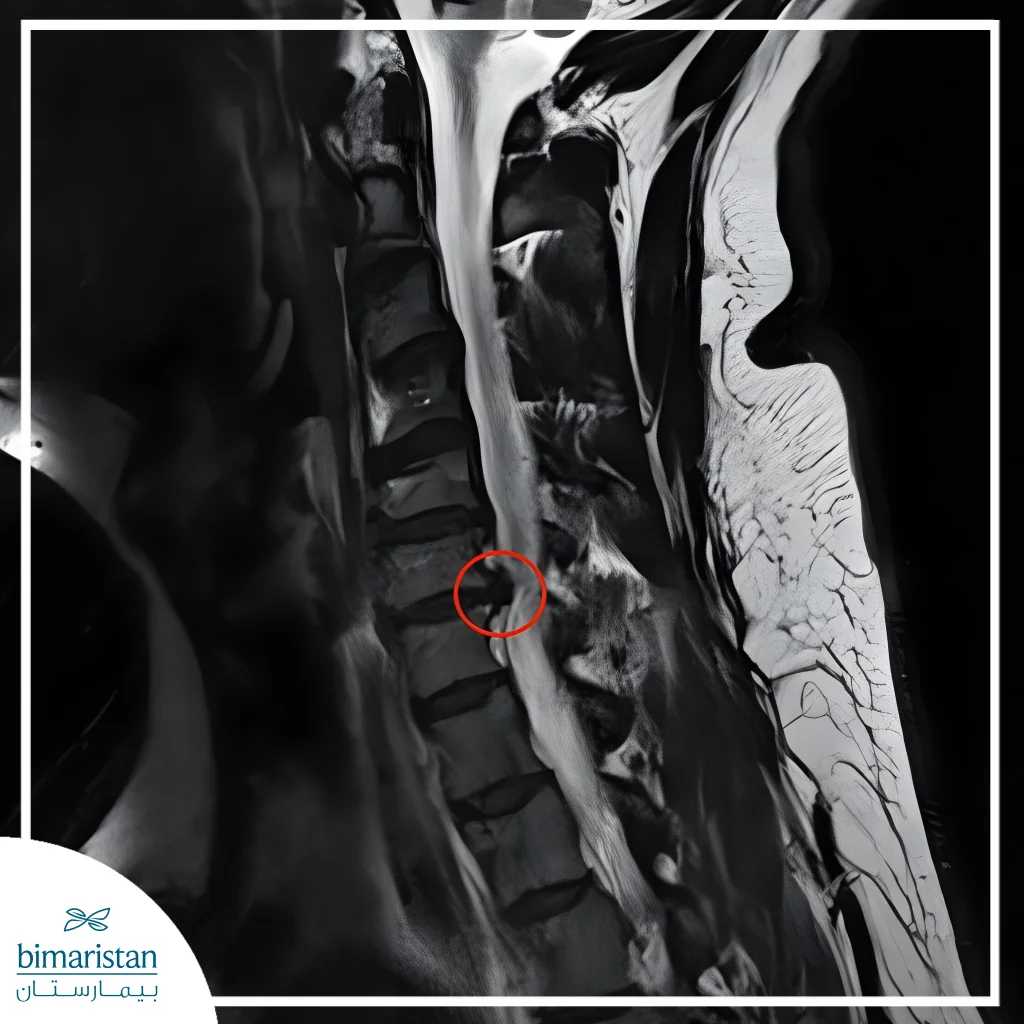

A cervical disc condition occurs when the disc between the cervical vertebrae slips, ruptures, or becomes damaged. This damage can cause the gel‑like nucleus to protrude and press on the spinal cord and surrounding spinal nerves. As a result, patients often experience neck pain, as well as numbness and weakness in the shoulders and arms. This condition may also be accompanied by other symptoms, including headaches, dizziness, and visual disturbances.

Regular examinations, such as MRI scans or neurological examinations, allow the doctor to accurately pinpoint the source of pain and develop a treatment plan that protects the spine. Early detection also prevents the need for future surgery, as the condition can be managed with physical therapy or lifestyle modifications in a timely manner.